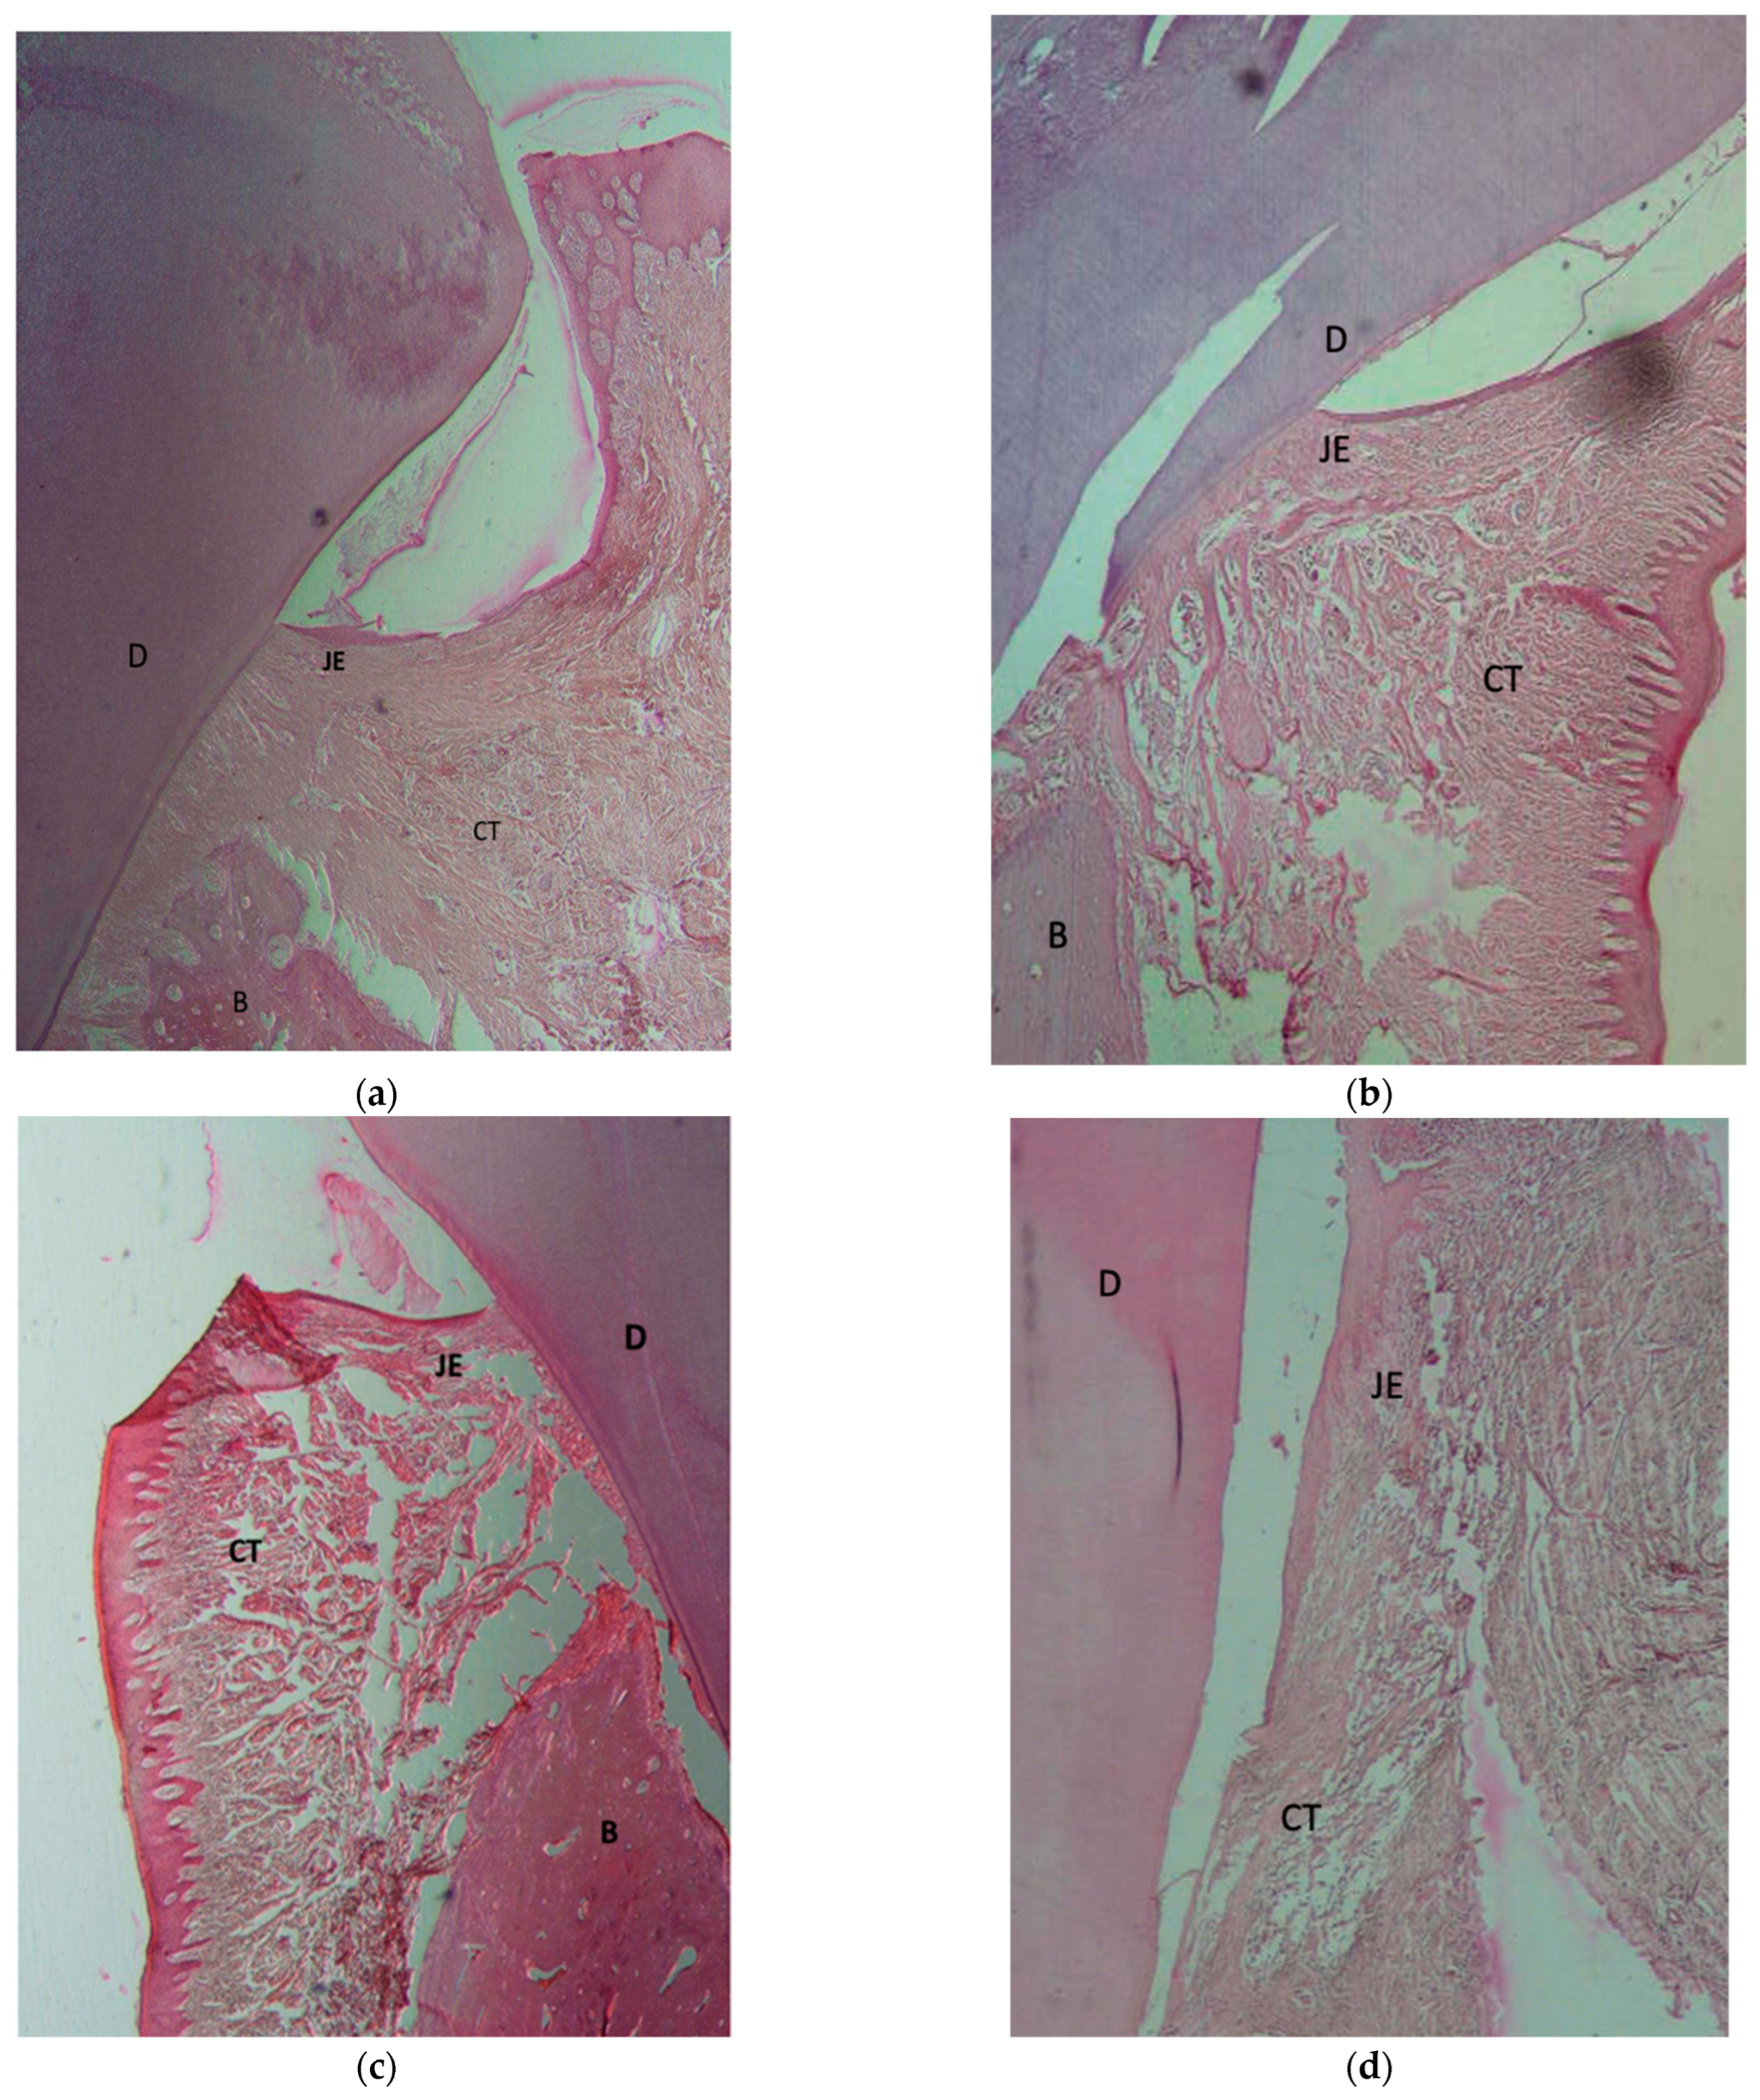

2.4. Histological Observation and Histomorphometric Assessments

3. Results